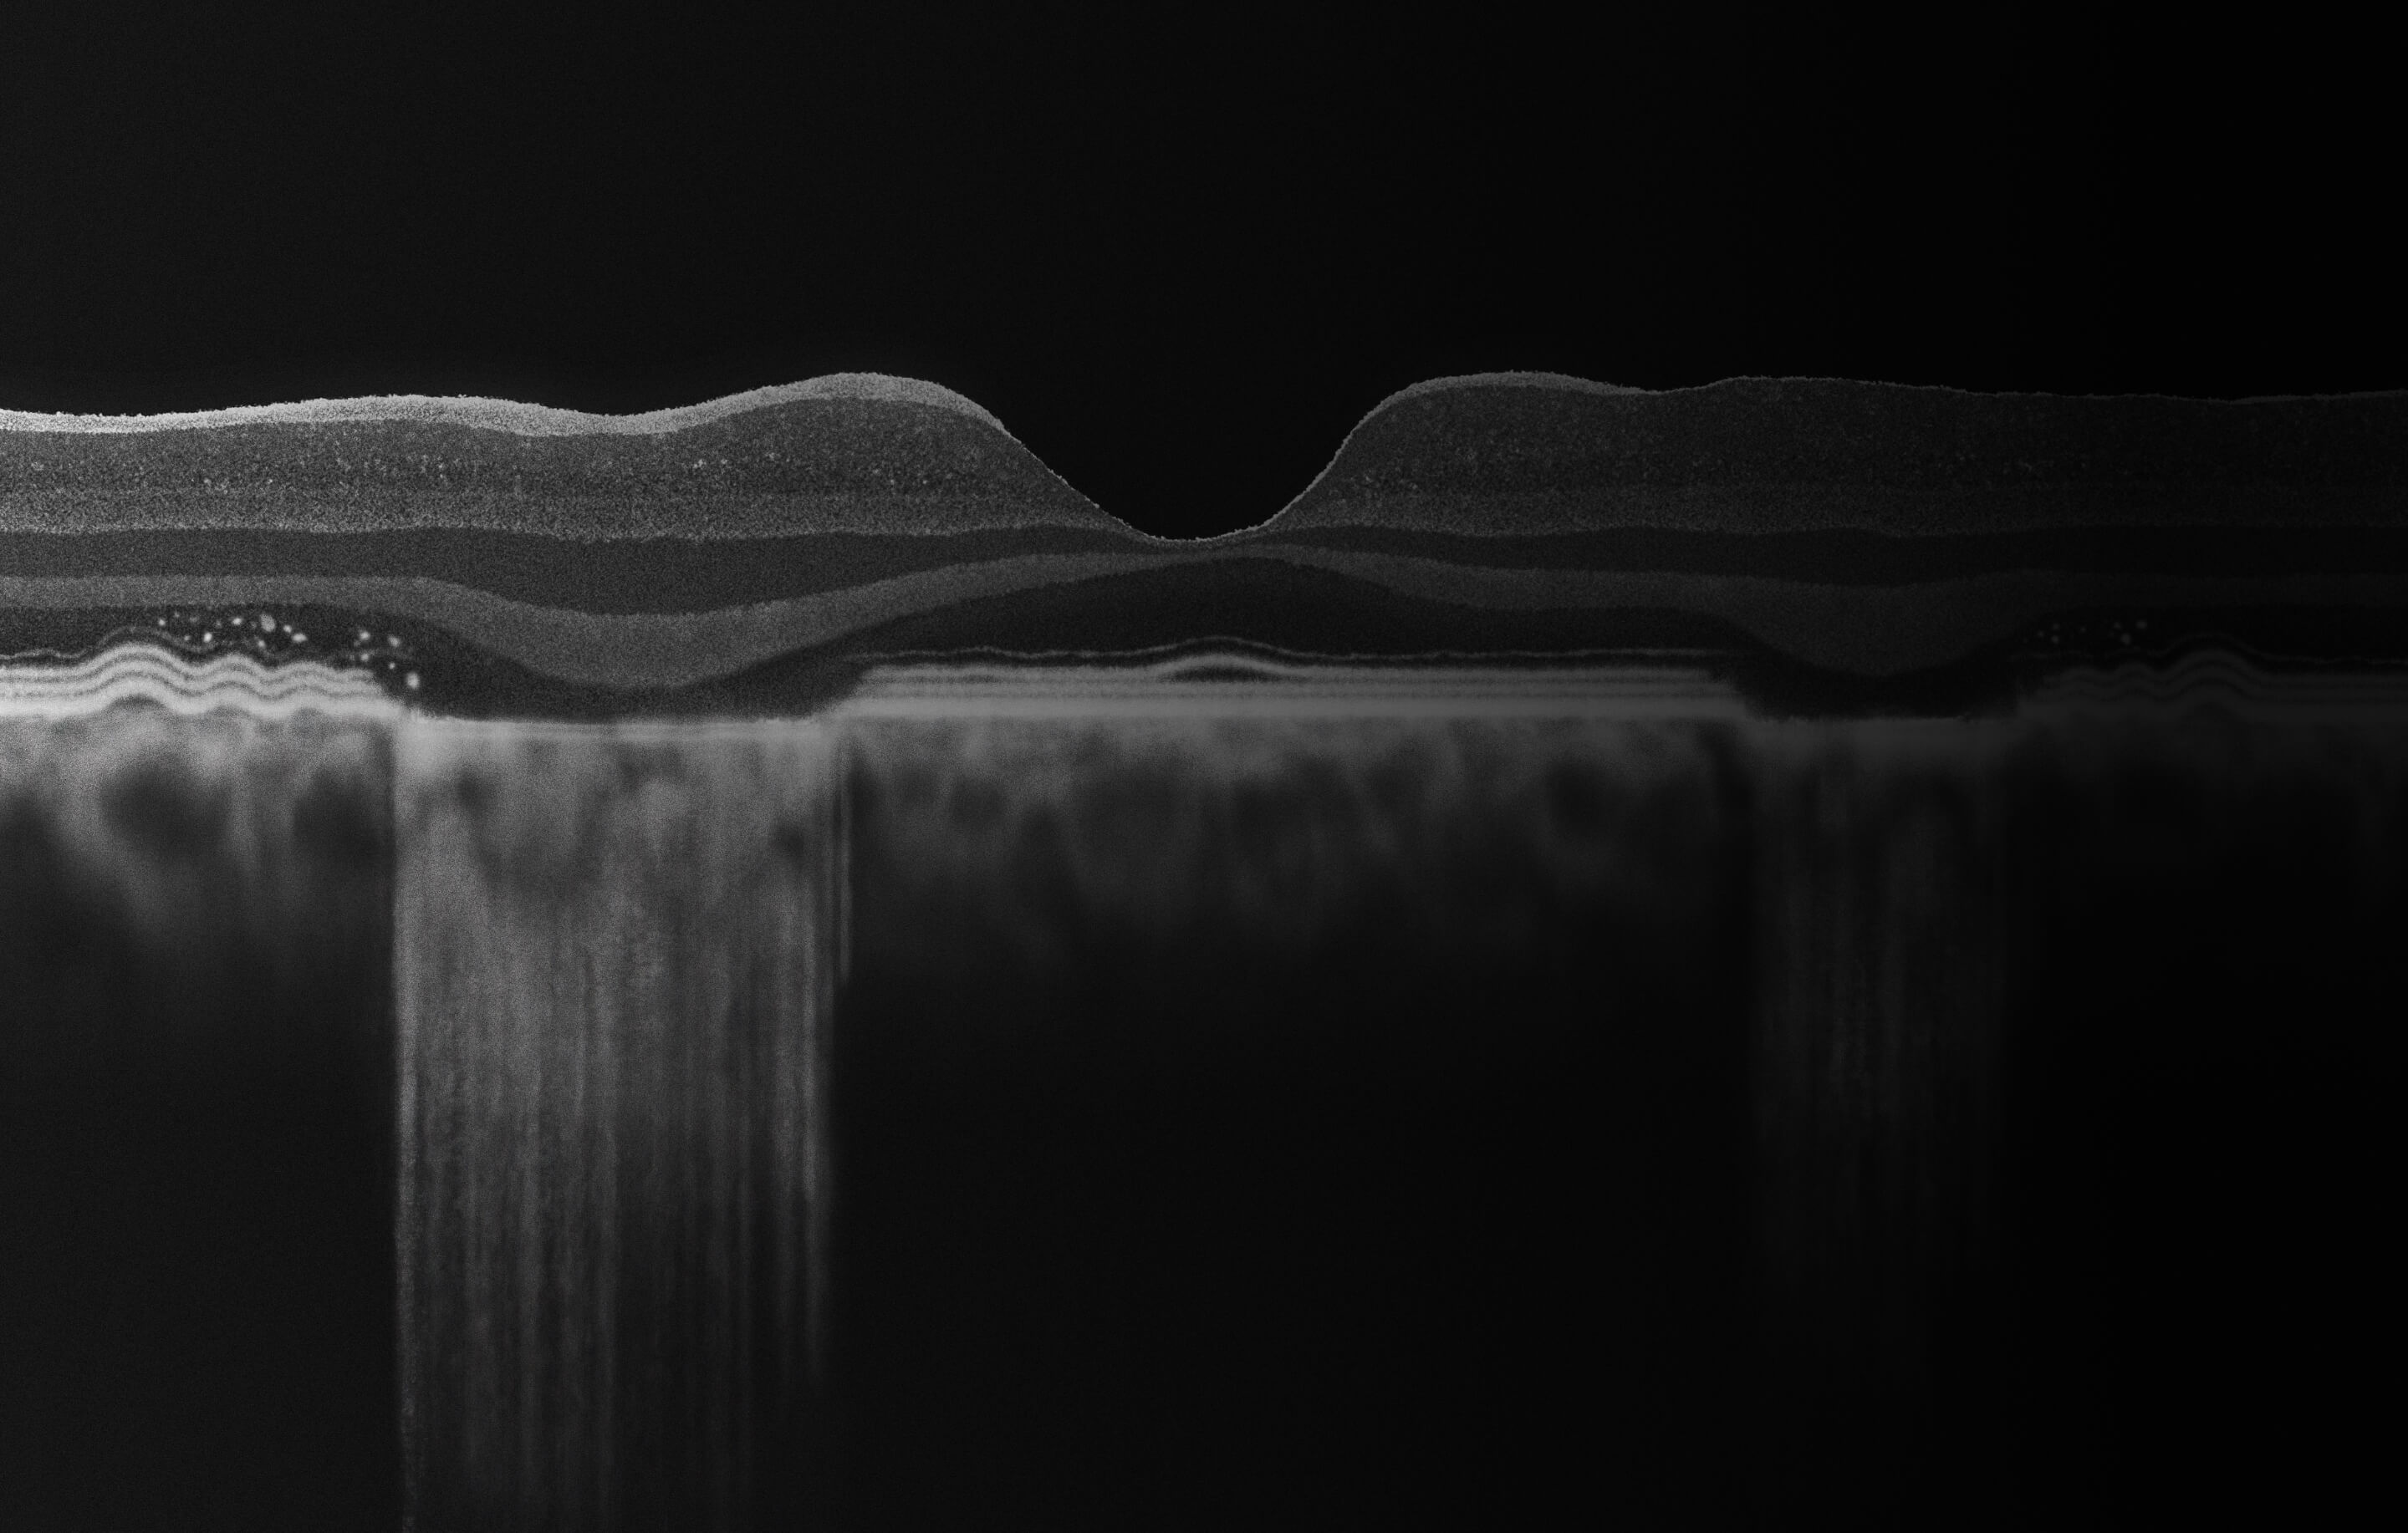

Learn how to recognize GA

OCT=optical coherence tomography.